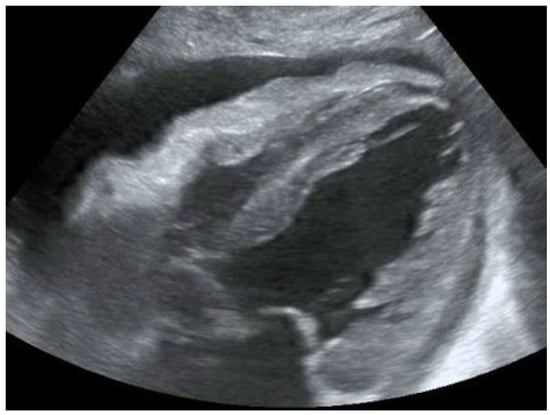

Another condition in which echocardiography can help the physician is the finding of hypoechoic material between the two layers of the pericardium, which allows us to make a diagnosis of pericardial effusion (Figure 1). Another advantage is that the ultrasound performed in the emergency room by the emergency doctor has a very high sensitivity (96%) and specificity (98%) towards this pathology [14].

Figure 1. POCUS echocardiography: subcostal projection with pericardial effusion.

Knowing how to identify a pericardial effusion also allows us to diagnose much more dangerous clinical pictures, such as cardiac tamponades [15].